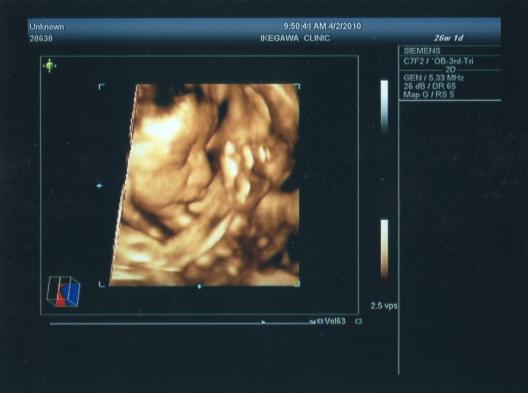

10 妊娠中期の検査・妊婦検診8回目(26週6日)~性別確定編~ ブログ内検索 結構いろいろ書いてます。Let's search!(^^)vSep 12, 17 · 妊娠26週は妊娠7ヶ月の最終週です。妊娠7ヶ月から健診の回数が2週に1回になり、より頻繁にエコー写真を見る機会が増えることでしょう。赤ちゃんの性別がわかるようになり、出産準備にもそろそろ本腰をいれる頃です。体重も増え、大きくなったお腹で移動するのは大変ですが、赤妊娠26週目に下腹部の痛みや不快感を感じたら、 ママの子宮内の羊水の量を超音波検査(エコー検査)で調べてもらいましょう。 妊娠26週目ママの症状 骨盤の痛み:出産に備えてママの骨盤の靱帯が緩み、柔らかくなっていきます。椅子に座ったり椅子

妊娠中期の検査 妊婦検診8回目 26週6日 性別確定編 ひまわりばたけ 妊娠 切迫早産入院 退院 出産日記 ブログ